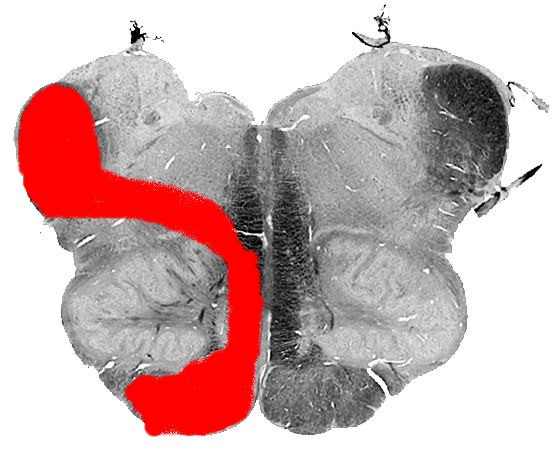

Пирамидная симптоматика в неврологии: ключевые аспекты

:background_color(FFFFFF):format(jpeg)/images/article/motor-cortex/XiebAmFl6VnmTW8eAak5Ww_thumbnail_T990_corticospinal_and_corticobulbar_tracts_PK.png)